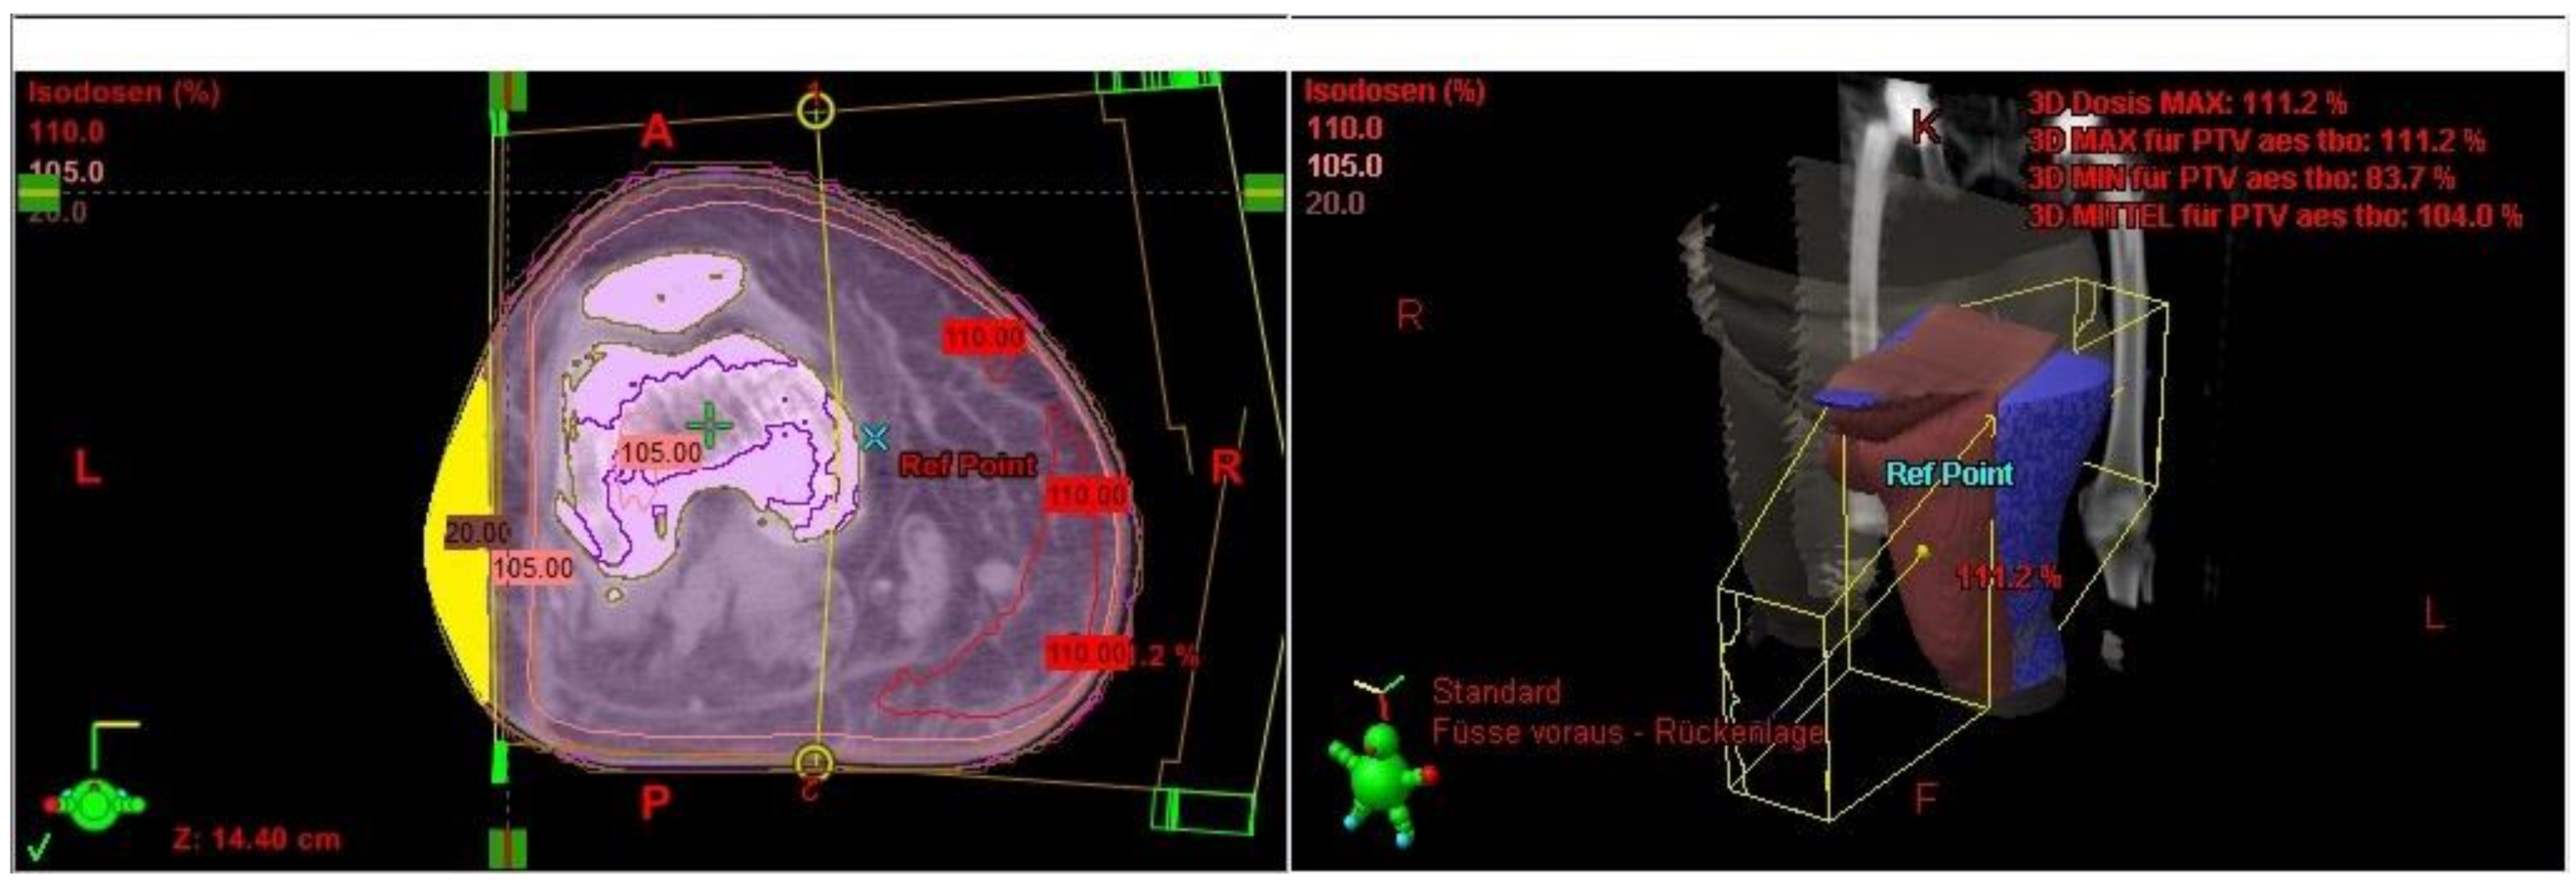

The Lymph-Sparing Quotient

Use of the Lymph-Sparing Quotient